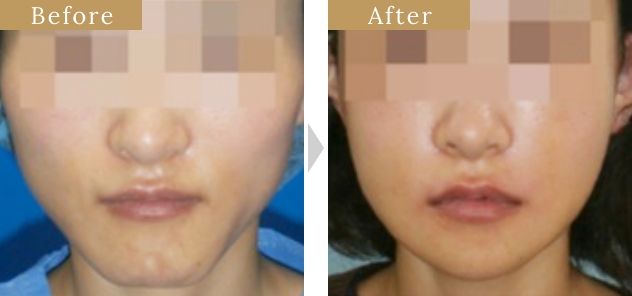

症例

症例